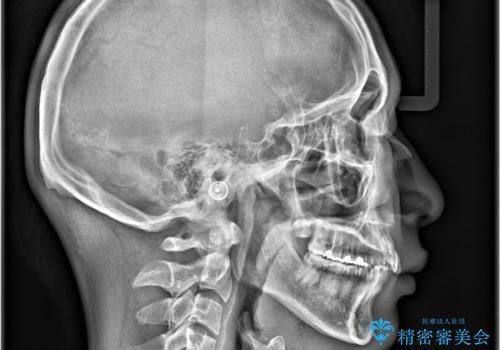

- 「上の前歯の捻じれと下の前歯のでこぼこを治したい」を主訴に来院された患者様です。

矯正検査の結果、非抜歯で矯正可能だったためインビザラインで治療を行いました。

アーチの拡大とIPRで叢生を改善いました。